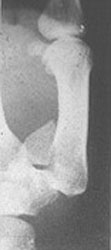

Bennet's fracture เป็นกระดูกหักที่ฐานของ first metacarpal bone พร้อมด้วย lateral subluxation ดังรูป sk 89

รูป sk 89  Bennet's fracture dislocation